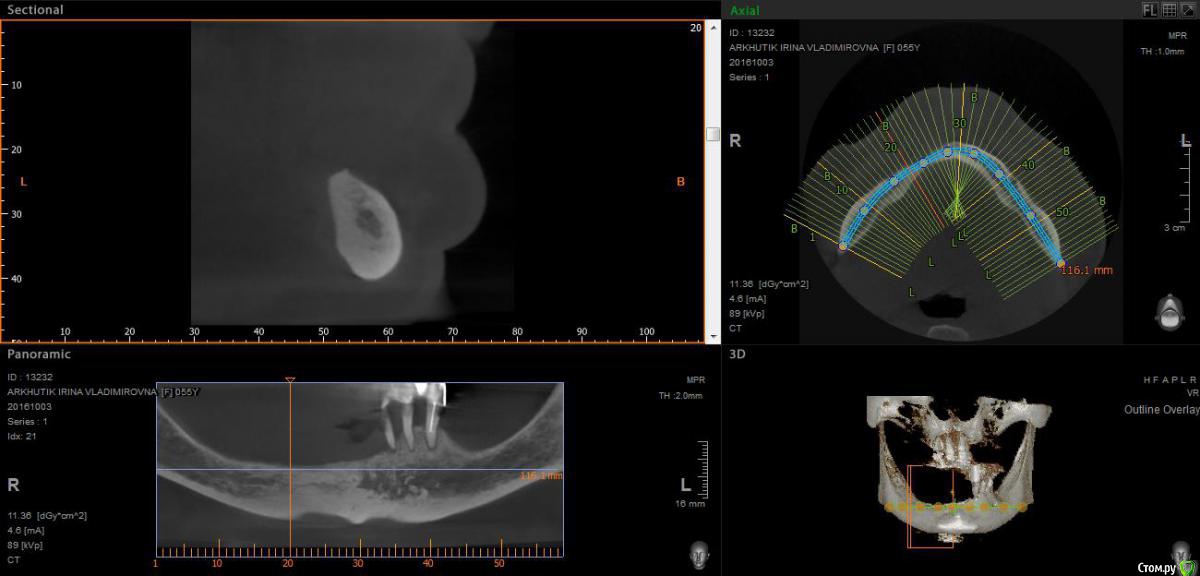

Rusty Опубликовано 5 октября, 2016 Поделиться Опубликовано 5 октября, 2016 Добрый день. К ортопеду обратилась пациентка 55-60 лет с такой ситуацией. Пришла с дочкой, дочь с мамой настаивали на несьемной конструкции, ортопед отправил на кт и вот. Не хочу планировать ей много хирургии, оцените и мой план пожалуйста и буду рад услышать советы по реабилитации пациента. По сути да) просто искал место куда есть возможность поставить, ортопед говорит тогда балка либо локаторы Ссылка на комментарий

Rusty Опубликовано 5 октября, 2016 Автор Поделиться Опубликовано 5 октября, 2016 На н/ч балка? Какие измерения в дист отделах? На в/ч мало четырёх. По три бы.На н/ч балка, в дистальных отделах над каналом около 3мм. На вч условий для установки больше 4 не нашел) Ссылка на комментарий